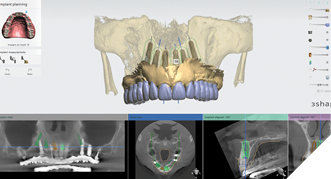

The data recorded during the clinical exam in conjunction with the FMS xrays and CT scan data were analyzed, and a diagnosis was made as to the viability of the patient’s existing teeth. A virtual diagnostic wax up was completed using prosthetic planning software (ExoCad) (Figs. 4A, 4B). The .STL file of the virtual wax up was integrated with the CT scan data in implant surgical planning software (3Shape Implant Studio) and a surgical plan was designed (Figs. 5A, 5B). The viability of this surgical plan was then evaluated in conjunction with the previously determined prognosis of the patient’s existing dentition and surrounding periodontium, and a treatment plan was formulated. The plan with the anticipated predictability of achieving the planned result was presented to the patient. The patient approved the treatment plan.

Fig. 5A

Fig. 5B